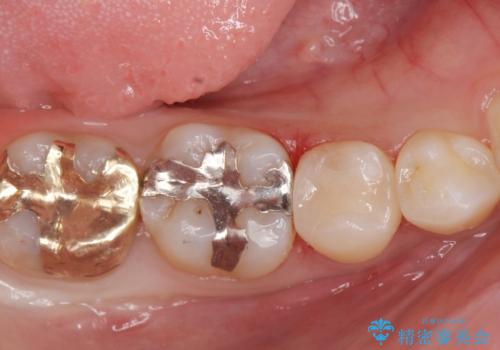

治療した歯は過去に樹脂で治療されていて、虫歯が再発していました。

樹脂の治療は経年的に劣化し、また歯質との隙間ができて虫歯の再発リスクが高いです。

e-max(セラミック)の治療は劣化をせず、歯質との隙間もできないため虫歯の再発のリスクが低いです。